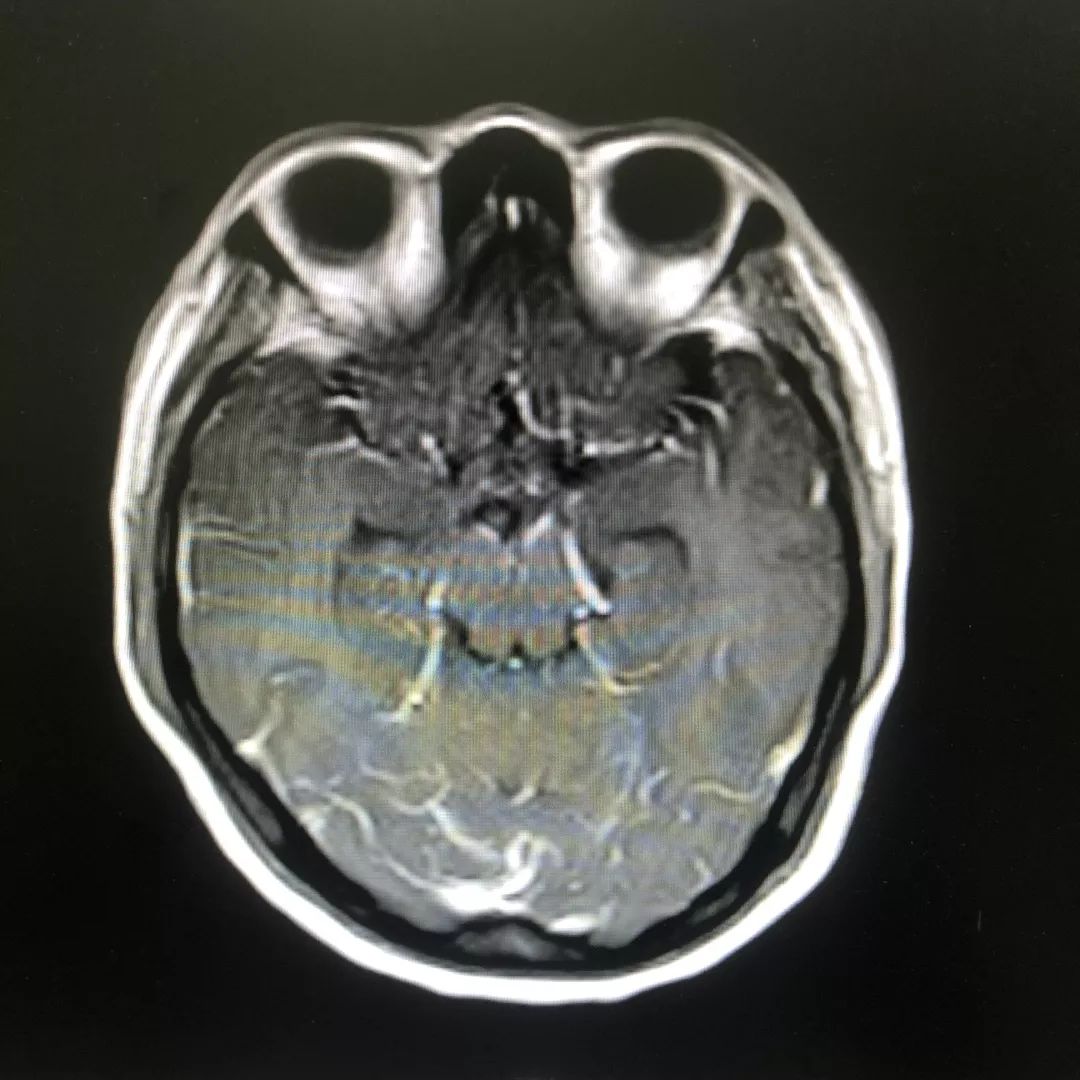

根据林女士发热、头痛,且出现精神行为异常、局部神经功能受损,查体可见明显的脖子僵硬,转颈和低头困难等症状,以及腰椎穿刺术及头颅磁共振增强检查等检查结果,医院神经内科专家高度怀疑结核性脑膜炎(一类难确诊、高病死率的疾病)可能,并立即启动了抗结核治疗。

头颅增强磁共振:脑膜多发线样增强影